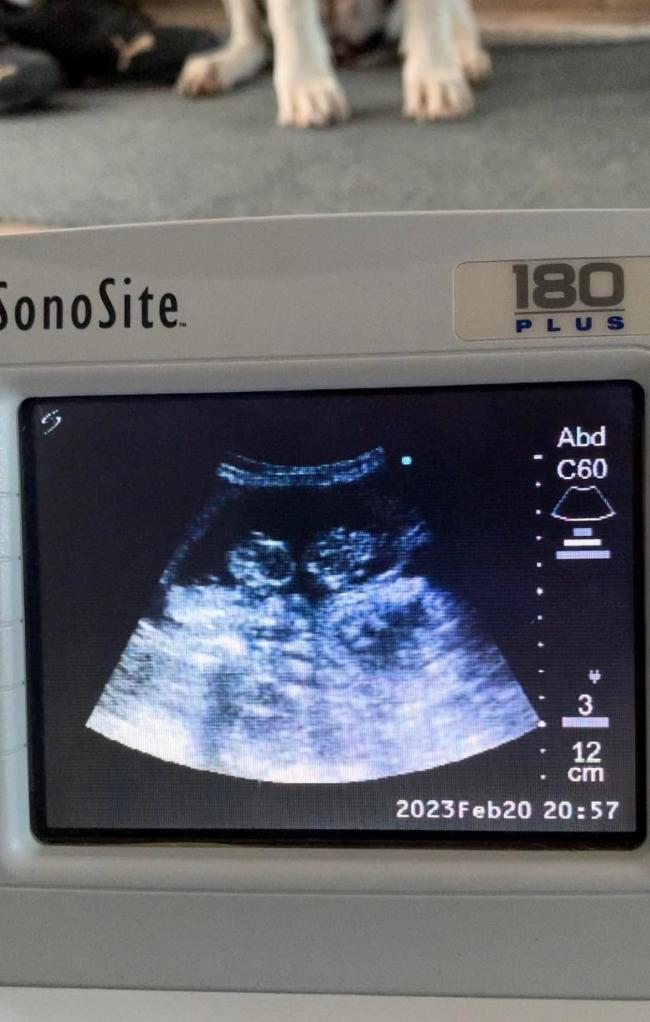

27.02.2023 Der 45. Tag der Trächtigkeit

Jetzt bin ich mir ganz sicher: zwischen zahlreichen weiteren M-chen haben wir ein Zwillingspaar. Die Fruchthöhle der beiden ist wesentlich größer als die der Geschwister und beide "Insassen" scheinen ziemlich gleich entwickelt. Zwillinge, das hatten wir bisher noch nicht, jedenfalls nicht wissentlich. Total spannend!!